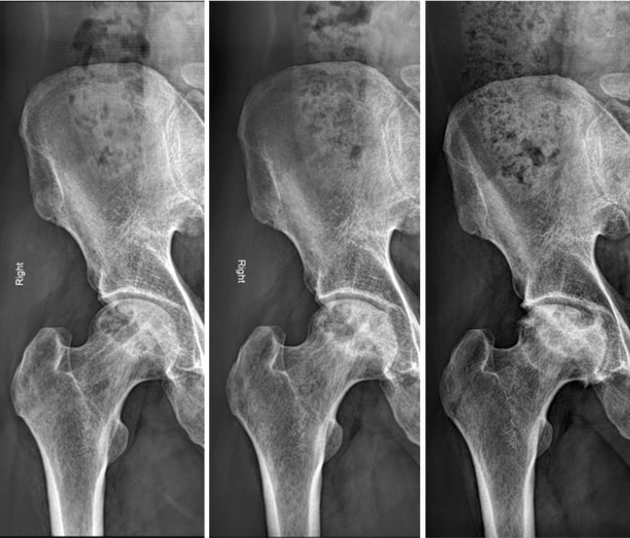

🔹 Radiografii simple:

- Se efectuează în incidențe anteroposterioare și „broască” (frog-leg) pentru ambele șolduri.

- NAV este adesea bilaterală (>60%), deci se investighează și șoldul aparent sănătos.

- Modificări radiologice:

- Timpurii: lucență (transparență osoasă), scleroză subcondrală

- Progresive: colaps subcondral (semnul „semilunii”), turtirea capului femural

- Tardive: îngustarea spațiului articular – stadiul final